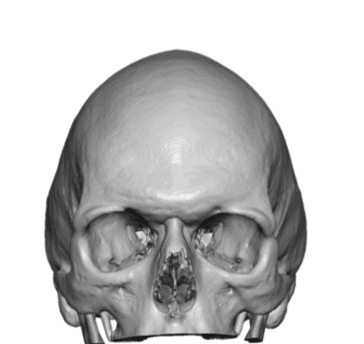

Patient 70

Adult with untreated sagittal craniosynostosis head shape.

Scaphocephalic skull reshaping with occipital and sagittal bone reductions with placement of custom skull implant.

Adult with untreated sagittal craniosynostosis head shape.

Scaphocephalic skull reshaping with occipital and sagittal bone reductions with placement of custom skull implant.